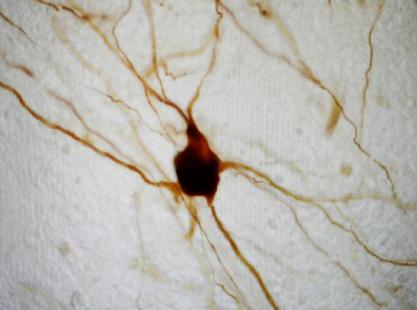

Les chercheurs ont étudié l’activité des neurones à dopamine sur des biopsies cérébrales d’un modèle murin à l’aide de l’optogénétique. Cette technique très utile permet d’activer sélectivement les cellules à la lumière après manipulation génétique. Contrairement à ce qui est habituellement pratiqué dans de telles expériences, les neurotransmetteurs non dopaminergiques n’ont pas été bloqués. Et lorsque les neurones à dopamine ont été activés, les scientifiques ont constaté non pas les effets attendus mais une inhibition rapide des neurones du striatum : un autre neurotransmetteur que la dopamine était à l’œuvre. Ces résultats ont tellement surpris l’équipe que les chercheurs ont lancé une série d’expériences complémentaires.